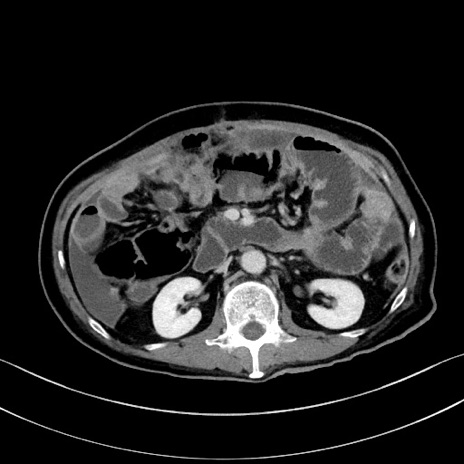

症例28(横断像)

【症例】60歳代男性

【主訴】嘔吐

【現病歴】胃癌にて胃全摘後。食思不振が悪化し、夜中に嘔吐することがある。

【既往歴】胃癌、胃全摘、脾摘、胆摘後

【データ】WBC 5900、CRP 10.56